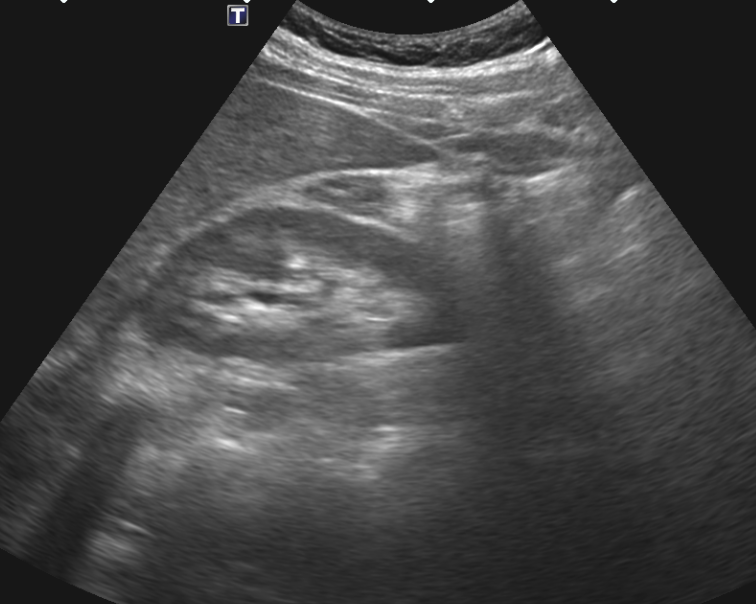

복부초음파 검사했는데요 초음파상 오른쪽신장 부근 사진인데 신장물혹이 보이나요?

혹시 복부초음파 오른쪽 신장부근 사진몇장올리는데.. 혹시 물혹이 보이시나요?

• 1번 째 사진

복부초음파 사진 여러 장 올린 것에 신장낭종은 잘 보이지 않는 것 같습니다